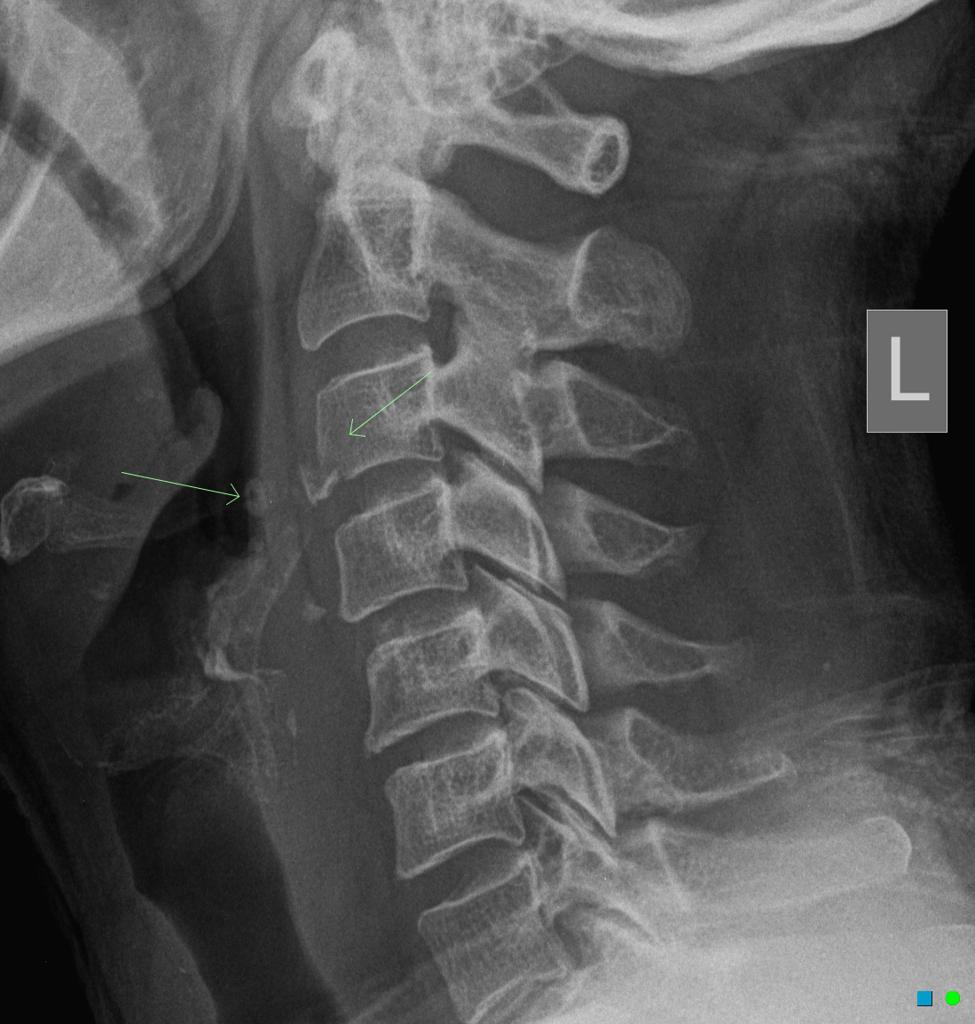

C2 and C6-7

most spinal fx occur where?

clay shoveler’s fx

avulsion fx of the spinous process C6-T1, results from hyperextension of the neck

hangman’s fx

fx of anterior arch/pedicles of C2 w/ or w/o subluxation of C2 on C3, occurs w/ extreme hyperextension

teardrop fx

comminuted vertebral body w/ triangular fragments extending from body; caused by compression & hyperflexion of c-spine, best demoed on lateral or CT